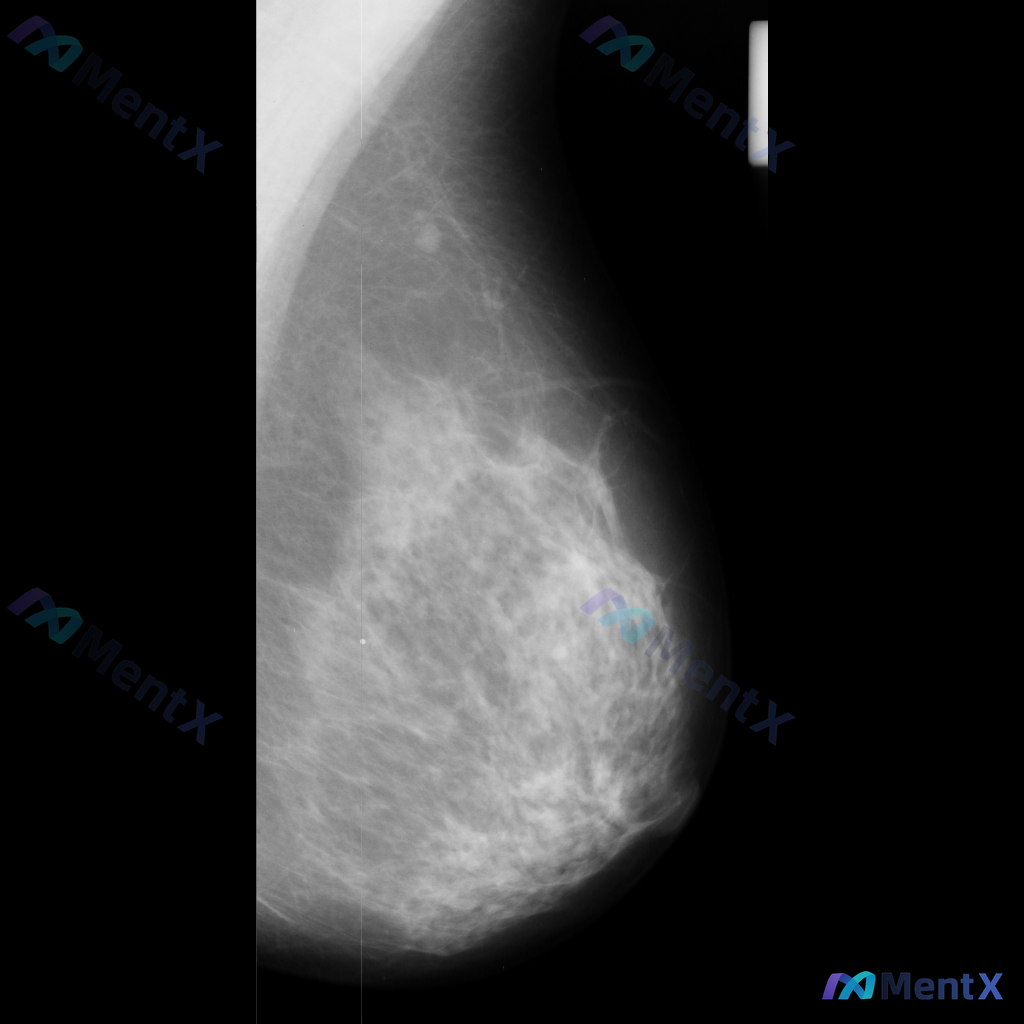

这张左乳MLO位X光片的异常表现,你会怎么考虑?

整理到一份乳腺影像资料,和大家讨论一下读片后的判断方向。 基本影像信息 - 体位:左乳内外斜位(MLO) - 影像质量:曝光和对比度良好,胸大肌边缘可见,无明显技术伪影 - 乳腺组织构成:散在纤维腺体/不均匀致密型 主要影像表现 在左乳头后方、乳晕附近,可见一类圆形/卵圆形密度增高影: - 边界似清...

整理了一份乳腺影像的读片资料,想和大家讨论下判断方向: 基本影像信息 - 单侧乳腺X光片,投照体位考虑可能为内外斜位(MLO) - 乳腺组织构成:不均匀致密型 - 影像质量:曝光适中,清晰度良好,无明显伪影 - 可见结构:皮肤、皮下脂肪层、乳头乳晕、Cooper韧带显示尚可;未见明确钙化血管或腋窝淋...